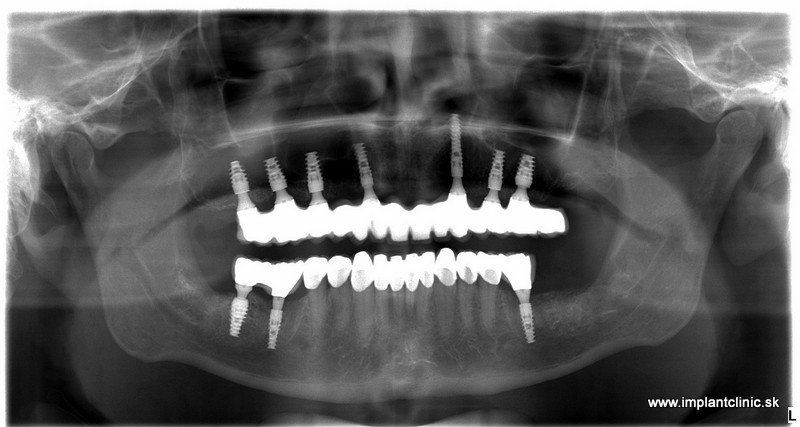

Na základe RTG a CT vyšetrenia náš hlavný implantológ MUDr. Marek Salka, odporučil pacientovi extrakcie nevyhovujúceho chrupu a následne celkovú rekonštrukciu hornej a dolnej čeľuste pomocou zubných implantátov s fixným keramickým oblúkom do vrchnej čeľuste a náhrada stoličiek v dolnom chrupe pomocou zubných implantátov a estetická úprava ostatných zubov pomocou zubných koruniek.

Plán ošetrenia pacienta Jakuba, a teda celková rekonštrukcia jeho chrupu, zahŕňal implantáciu 7 zubných implantátov do hornej čeľuste a 3 zubné implantáty do sánky. V spodnej čeľusti mal pacient na pláne ošetrenia naplánovaných ešte 10 zubných koruniek.

Pred implantáciou sa pacientovi extrahoval zostatkový chrup.